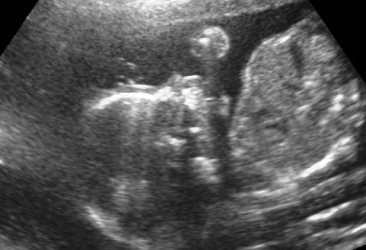

Прегледот на ултразвук во оваа фаза од бременоста најпрво опфаќа мерење на обемот и пречникот на главчето на бебето. Потоа се врши мерење на мозочните структури на бебето, што е особено значајно за откривање на некои тешки вродени малформации на централниот нервен систем. На оваа контрола се мери обемот на стомачето (AC), должината на бутната коска (FL) и должината на коската на надлактицата (хумерус). Овие мерки и нивниот меѓусебен однос даваат значајни информации за растот на бебето. Потоа внимателно се следи континуитетот на рбетниот столб, со цел исклучување на вродените малформации на рбетот (spina bifida). Понатаму може да се прикажат и внатрешните органи, како што е желудникот, мочниот меур и срцето на бебето, кое веќе има јасен четирикоморен пресек со визуелизација на двете предкомори и двете комори. Со доплер се испитува работата на срцето и протокот на крв во папочната врвка. На овој преглед се прикажува и полот на бебето, со доста јасна диференцијација на машките или женските надворешни полови карактеристики.